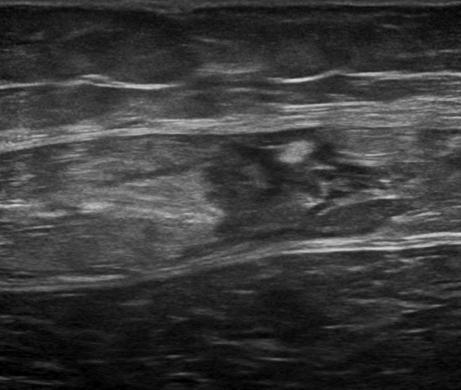

Chấn thương thành bụng

» Thông tin: Nam giới – 50 tuổi.

» Lâm sàng: Chấn thương thành bụng.

# Đụng dập, tụ máu cơ thành bụng.